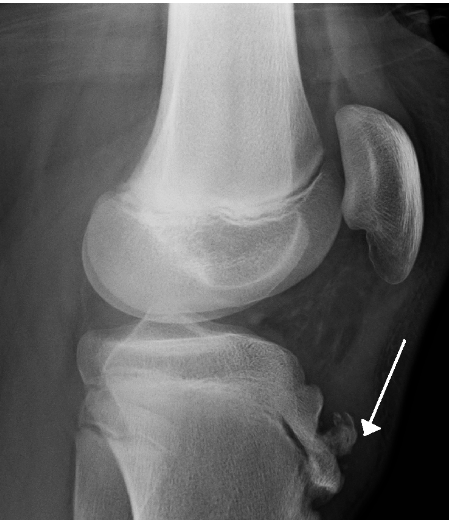

Q

the arrow is pointing to:

osgood-schlatter

blounts disease

SUFE

Perthes

CDH

A

osgood schlatter

15